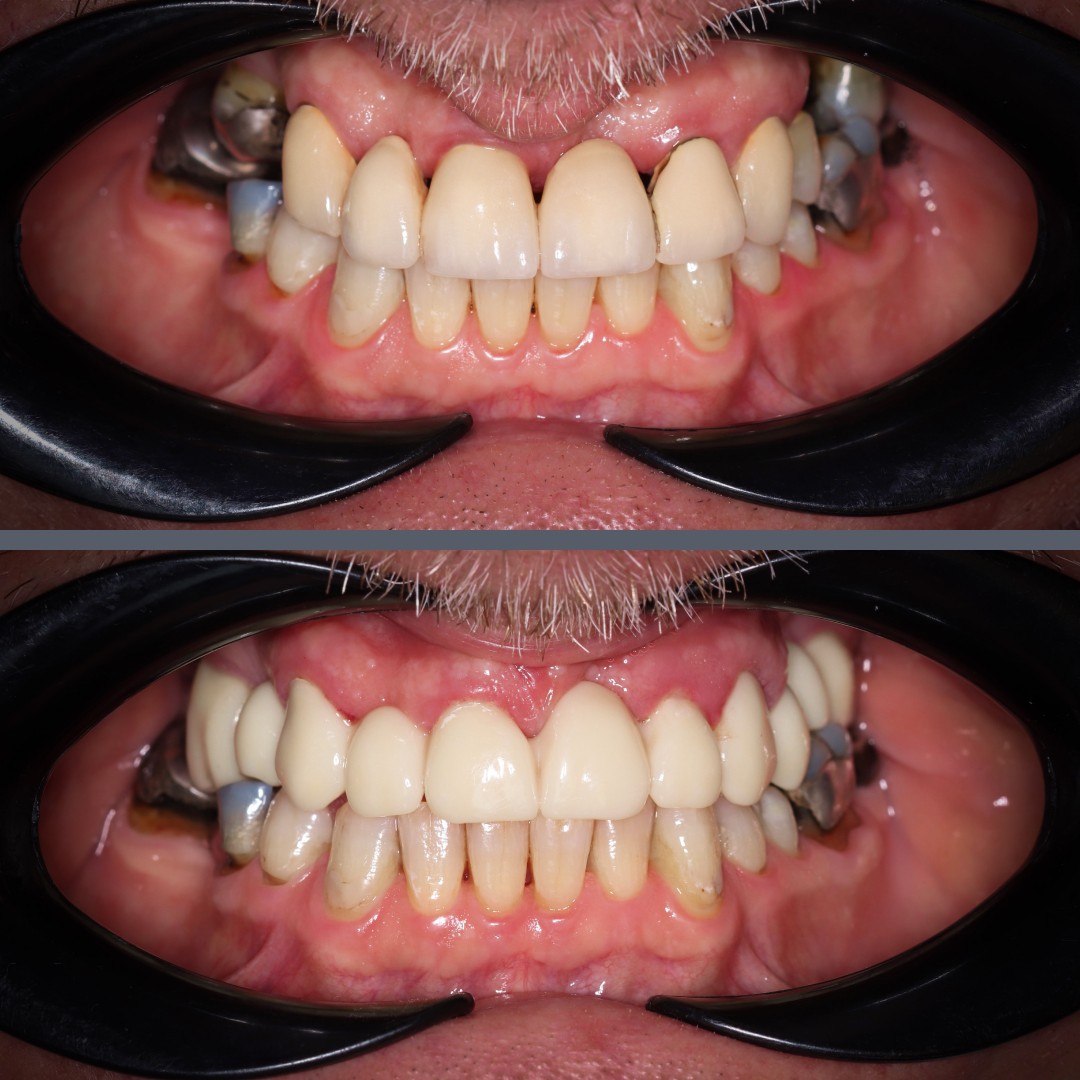

Solution

In the initial phase, we extracted the unsalvageable upper teeth. To support healing and ensure patient comfort, we placed temporary crowns – which already made a noticeable difference in the patient’s appearance and overall well-being.

At the second visit, we completed the treatment with permanent restorations: a full-arch bridge made from metal-free zirconia for the upper jaw and individual zirconia crowns for the lower jaw.

Result

The rehabilitation was completed in four months, fully restoring the patient’s chewing and bite function. As a result, the patient regained his confidence and quality of life.